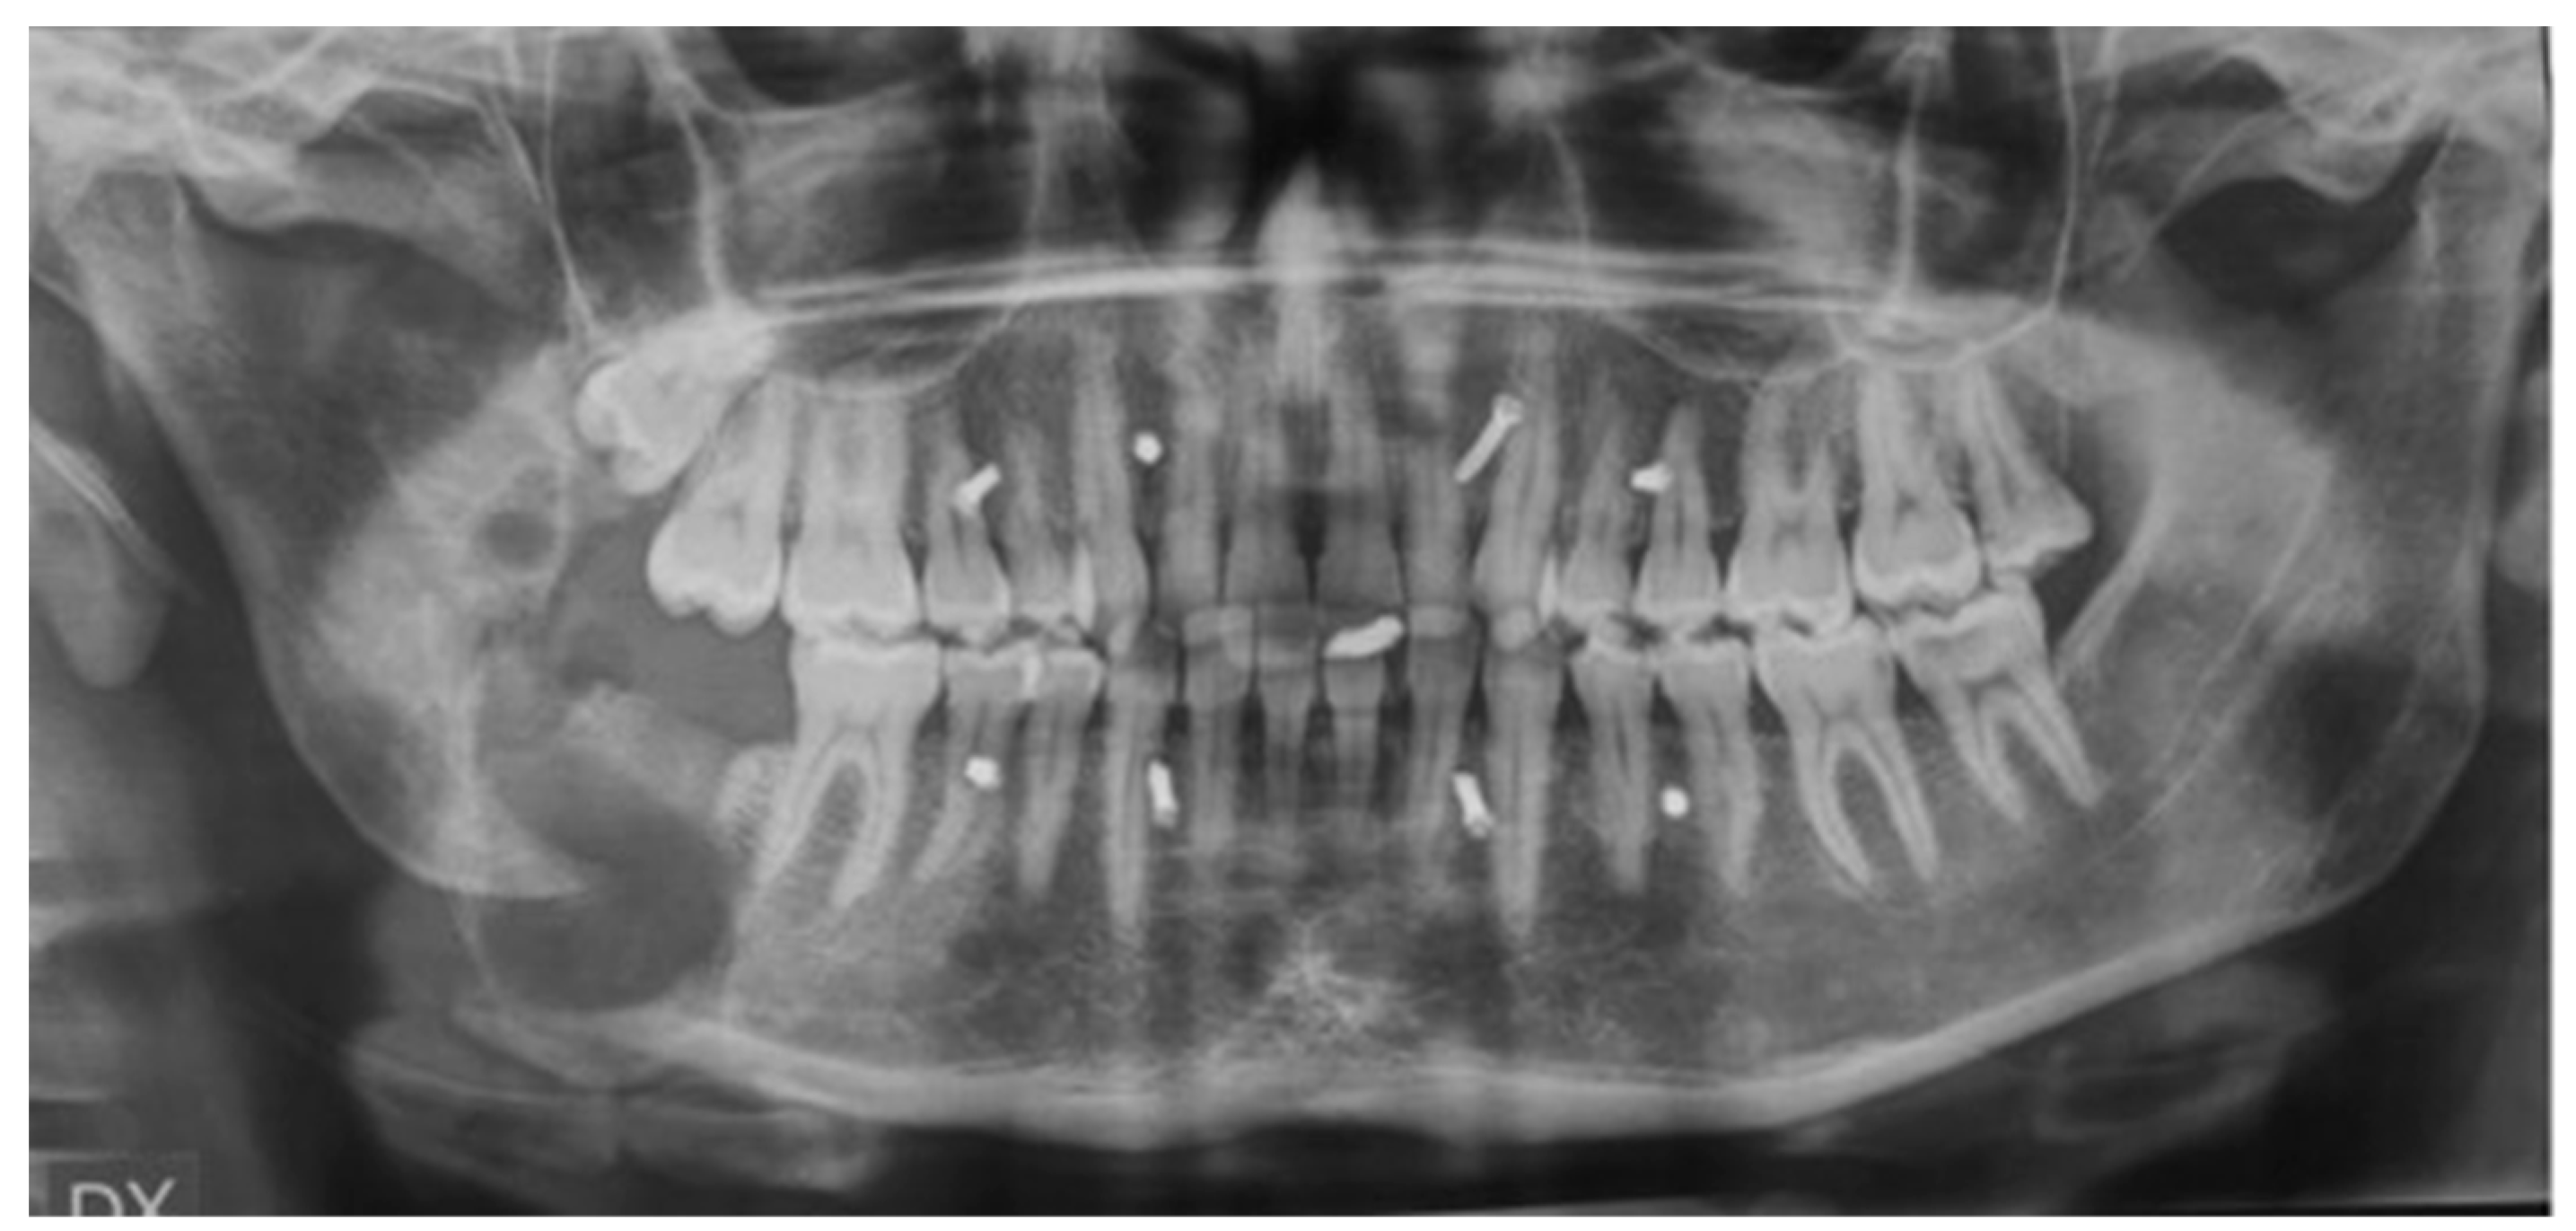

2.6. Patient #2